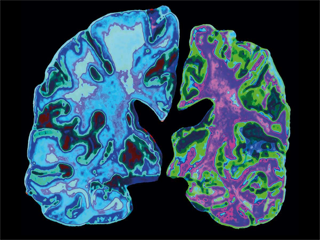

As per a new study led by School of Public Health researcher, Johns Hopkins Bloomberg; the development of dementia, often caused by Alzheimer's disease, is caused by abnormal blood levels with dozens of proteins that can detect potential diseases. So far, it has not been known that proteins are associated with dementia, which suggests new targets for preventive therapies. The results are based on new analyzes of blood samples from more than 10,000 young and old-aged people which were collected and stored decades ago in larger studies as part of an ongoing study. Out of 38 proteins found in blood, 16 seemed to predict the risk of Alzheimer's disease two decades in advance. Although most of these risk markers are just incidental by-products of the slow disease process that leads to Alzheimer's disease, the analysis indicated high levels of the protein SVEP1 as a possible causal contribution to this disease process.

This is the most comprehensive analysis till date, and sheds light on several biological pathways linked to Alzheimer's, says study director Josef Coresh, MD, PhD, MHS, George W. at Bloomberg School. Some of these proteins discovered were just indicators that disease might occur, but a subset could be causally relevant, which is exciting because it increases the ability to target these proteins with future treatments.

It is estimated that more than six million Americans have Alzheimer's, the most common form of dementia, which is an irreversible fatal disease that leads to loss of cognitive and physical functions. Despite decades of intense study, there are no treatments that can slow down this disease process. So, scientists widely believe that the best time to treat Alzheimer's is before symptoms of dementia develop in human body. Amyloid beta protein clusters scientists have shown that imaging the brain of plaques and amyloid beta or tau levels in the blood or cerebrospinal fluid has some value in predicting Alzheimer's disease years in advance. But humans have tens of thousands of other different proteins in their cells and blood, and the techniques of measuring many of them from a single small sample of blood have advanced in recent years. A thorough analysis using these techniques could reveal other originators to Alzheimer's disease, hopefully.